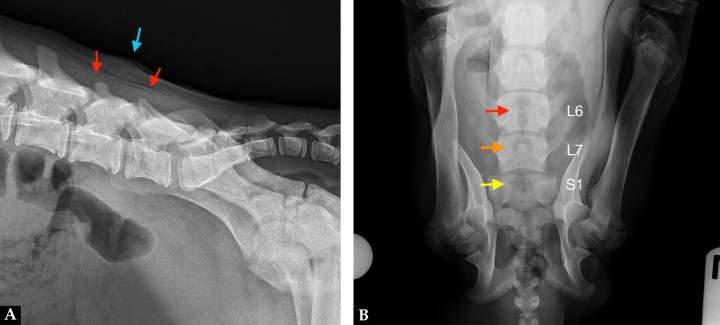

Mismas imágenes que la Figura 1. (A) Radiografía lateral derecha de la región lumbosacra. La apófisis espinosa de la sexta como de la séptima vértebra lumbar tienen una altura reducida (flechas rojas). Disminución de la radiopacidad a nivel de las apófisis articulares entre L6 y L7. El borde cutáneo dorsocaudal a L6 se observa irregular y el tejido blando subcutáneo presenta un aumento de su radiopacidad (flecha azul). (B) Radiografía dorsoventral de la región lumbosacra. Fémures posicionados en dirección craneolateral a la pared abdominal, cóndilos rotados medialmente y rótulas laterales a la diáfisis distal. Sobre el cuerpo y en la línea media de L6 se observa un área radiolúcida con forma de ojo de cerradura y no se identifica la apófisis espinosa (flecha roja). La apófisis espinosa de L7 es corta y redondeada (flecha naranja). En la línea media de la primera vértebra sacra (S1) se observa un área radiolúcida y no se visualiza la cresta medial sagital (flecha amarilla)